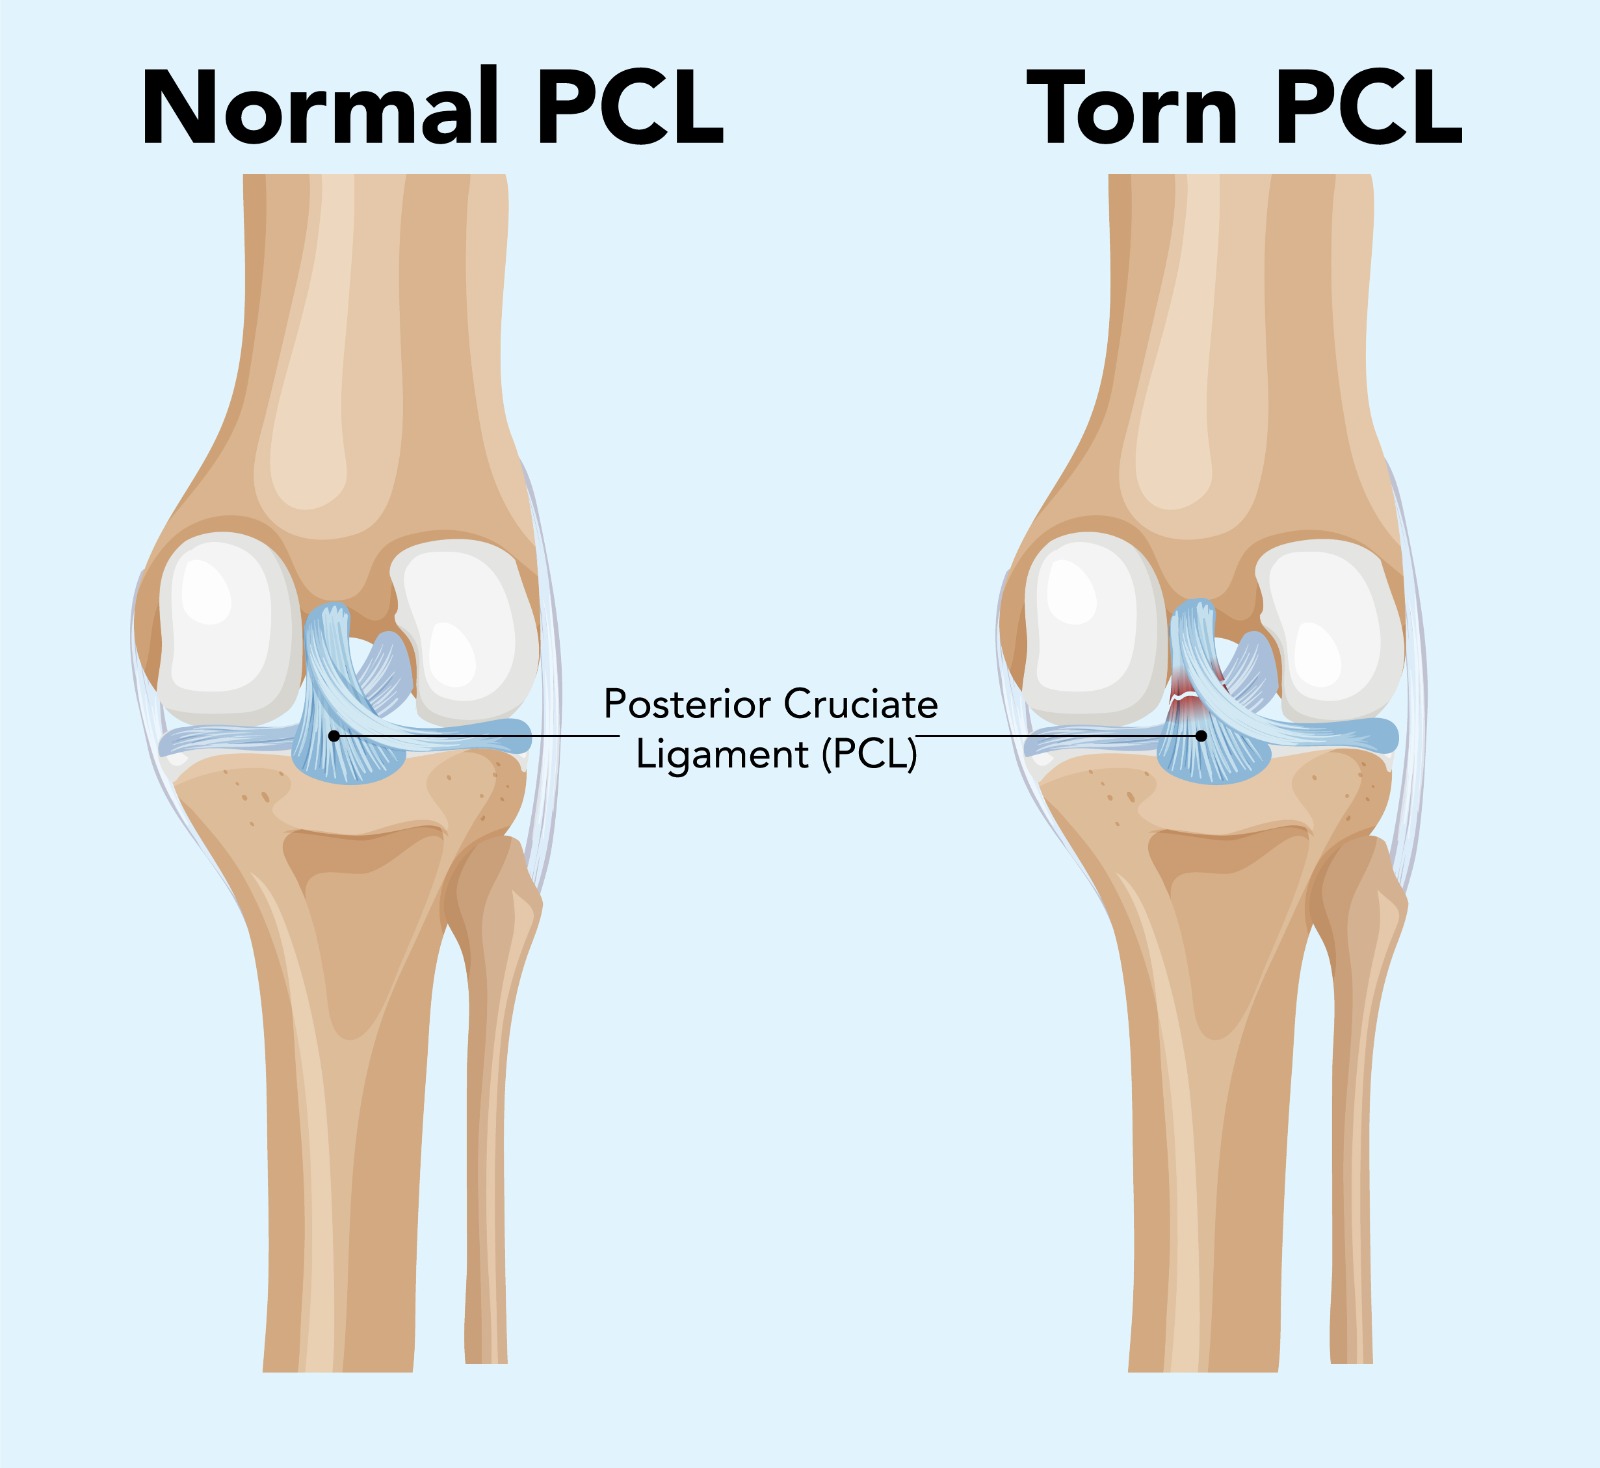

The posterior cruciate ligament (PCL) is the strongest ligament in the knee, preventing the tibia from sliding backwards relative to the femur. PCL injuries, though less common than ACL tears, account for a significant proportion of serious knee ligament injuries — particularly in contact sports, road traffic accidents, and high-energy trauma. They range from isolated grade I sprains to complete grade III ruptures, often occurring alongside injuries to other knee ligaments in complex multi-ligament knee injuries.

The posterior drawer test and posterior sag sign are the key clinical tests. Stress X-rays quantify the degree of posterior tibial translation. MRI confirms PCL injury and identifies associated ligament, meniscal, and chondral pathology. CT angiography may be required if knee dislocation is suspected.